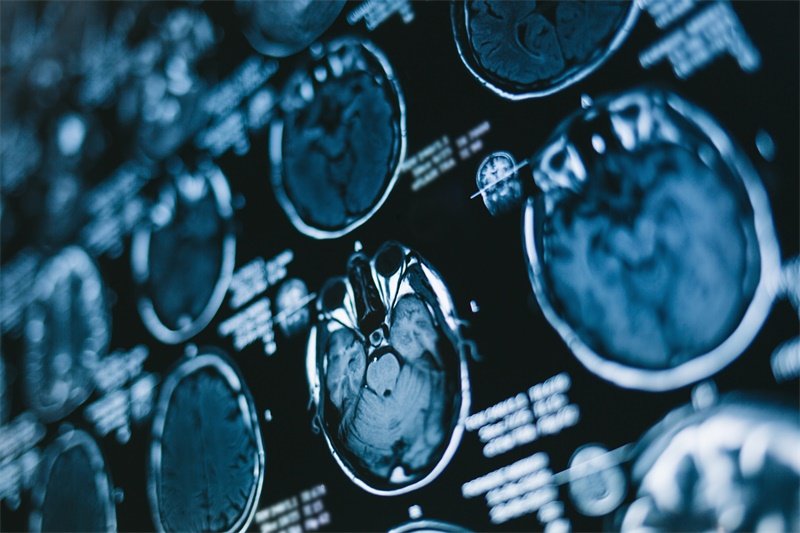

CT(计算机断层扫描)是一种非侵入性的方法,用于观察身体内部的结构。对于脑部的检查尤其重要,能够提供高分辨率的图像,帮助医生快速识别问题。

在检测蝶鞍区占位时,CT图像可以显示出肿块的大小、位置以及与周围结构的关系。这有助于判断肿块是良性还是恶性,也能揭示是否影响了重要的生理功能。